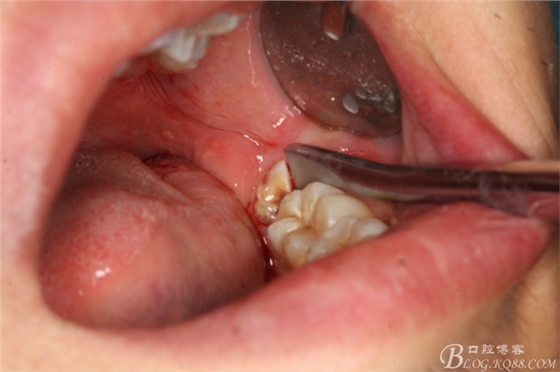

圖14.挺子放頰側(cè)骨板,以頰側(cè)骨板做支點(diǎn)

圖15.采用楔法、挺法等手法、挺松牙根